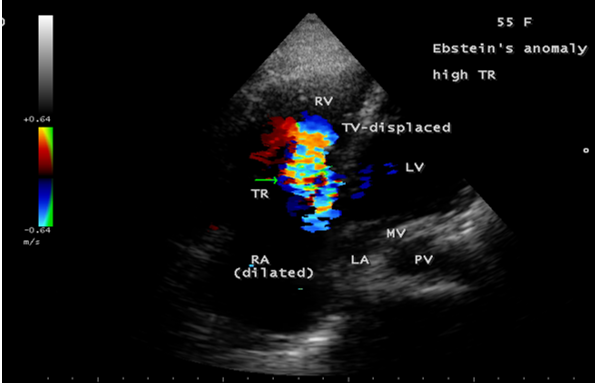

Case 3 (55-year old female with Ebstein’s anomaly)

A 55-year old asymptomatic, acyanotic female, given birth to three children, presented with grade 2/6 systolic murmur at the lower left sternal border. 2D echocardiography revealed a septal tricuspid leaflet tethering and a high moderate tricuspid regurgitation as shown in Figures 9 and 10 suggesting an Ebstein’s anomaly.

The tricuspid orifice is typically incompetent as in Figures 3, 5 and 10, occasionally stenotic, and rarely imperforate as in Figure 16 [44],[45]. The true anatomic tricuspid annulus occupies its normal position at the right atrioventricular junction and it is less well defined than in a normal heart. The annulus tends to be appreciably dilated and contribute to the development of valvular incompetence. In extreme downward displacement of posterior and septal leaflets, the closure of the tricuspid annulus depends on the size and potential excursion of anterior leaflet. When the chordal attachments are short and the leaflets contain multiple or large fenestrations, adequate valve closure is impossible to achieve and varying degrees of regurgitation results. Color flow imaging and Doppler interrogation can establish the relatively low velocity regurgitant flow as in Figure 6, which begins at the level of the displaced septal and posterior leaflets as in Figures 5 and 10 and courses through the atrialized right ventricle into the right atrium proper as shown in Figure 5. Tricuspid regurgitation increases by annular dilatation [46]. During contraction of the atrium, the atrialized portion of the right ventricle balloons out and acts as a passive reservoir. Functional improvement of right ventricle depends on the severity of tricuspid regurgitation and on the ratio of the combined areas of right atrium and atrialized right ventricle relative to the areas of functional right ventricle and left ventricle [47]. Celermajer, et al described an echocardiographic grading score for neonates with Ebstein’s anomaly as shown in the Table 5 [48].

The functional impairement of right ventricle and regurgitation of tricuspid valve retard the forward flow and the overall effect is right atrial dilatation as shown in Figure 4. In many cases, the right atrial enlargement is extensive, but the mural thrombus is not a feature even in right ventricular dilatation. The enlarging right atrium becomes sufficiently compliant to accomodate a large volume of regurgitant flow with little or no increase in pressure as shown in Figure 6., In patients with marked Ebstein’s malformation and severe tricuspid regurgitation, liver and portal circulation are extensively affected, congestive hepatosplenomegaly and microscopic hepatic fibrosis eventually occurs in chronic cases with hypersplenism [49].